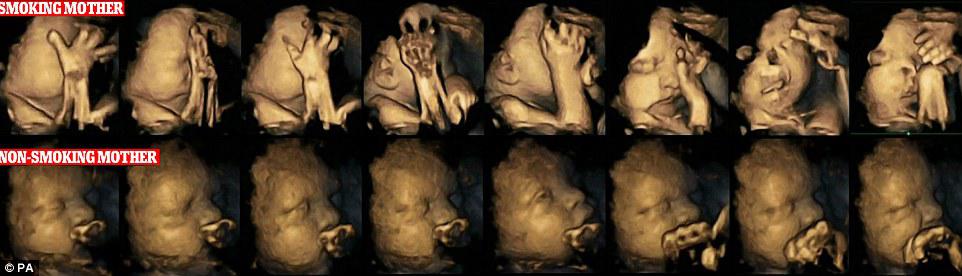

Внутриутробные 4-D УЗИ изображения лица ребенка показывают, как курение во время беременности вредит развитию ребенка в утробе.

Новые ультразвуковые изображения показывают, что дети матерей, которые курят во время беременности, трогают свой рот и лицо гораздо чаще, чем дети некурящих.

По словам экспертов, сканирование показывает, как курение во время беременности может задерживать развитие центральной нервной системы ребенка.